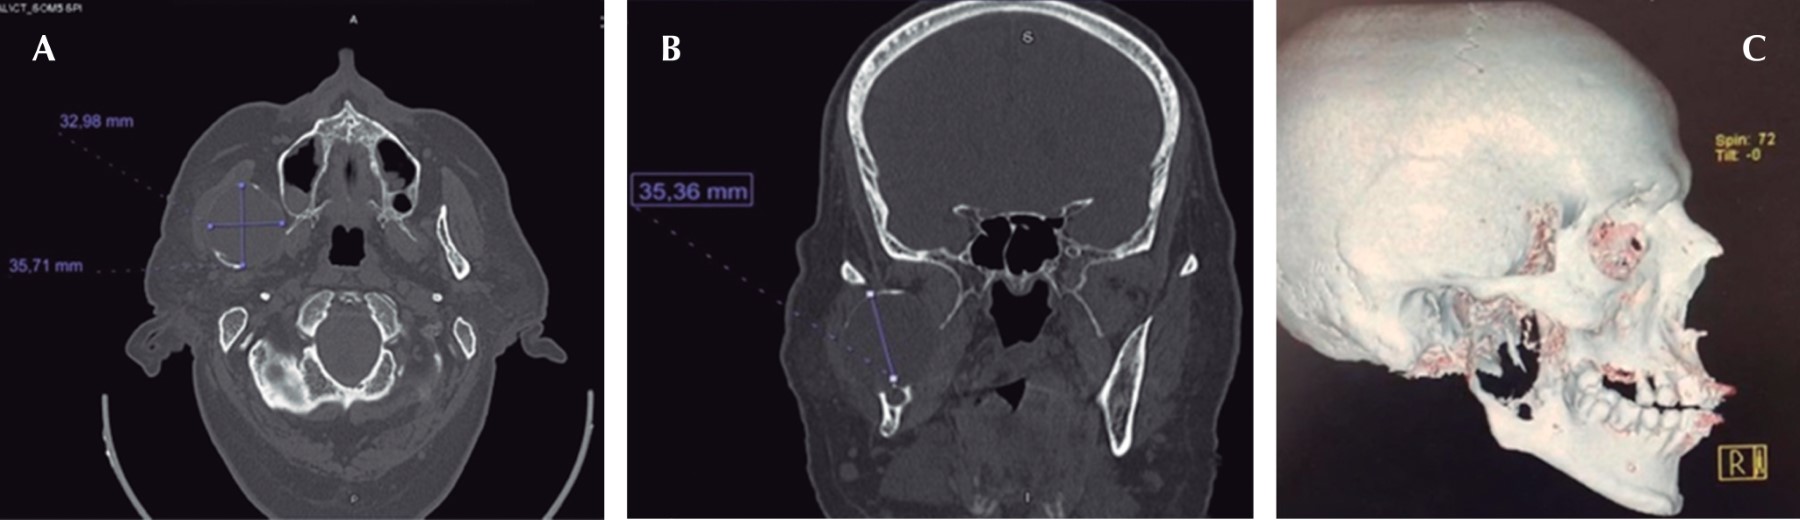

Inició padecimiento 19 meses previo a su primera valoración refiriendo chasquido súbito tras apertura máxima de la cavidad bucal, presentando dolor y aumento de volumen en la región posterior de la mandíbula derecha. En ortopantomografía se observa una zona radiolúcida, multilocular que abarca la rama ascendente derecha de la mandíbula y porción posterior del cuerpo mandibular con desplazamiento de tercer molar hacia borde cervical mandibular (Figura 1). En tomografía computarizada se observa lesión patológica multilocular que abarca la rama ascendente de la mandíbula, apófisis coronoides y hasta el cuello del cóndilo, la de mayor diámetro es de 35 × 32 mm con perforación de corticales casi en su totalidad y expansión de las corticales residuales (Figura 2). Se procede a realizar toma de biopsia incisional con un resultado de ameloblastoma folicular con datos de atipia celular (Figura 3), por lo que se decide solicitar gammagrama óseo que muestra una captación anormal en la rama mandibular derecha desde el cóndilo que correlacionan con la tumoración presente, así como un resultado negativo a la extensión metastásica ósea (Figura 4). Se decide realizar hemimandibulectomía y colocación de placa de reconstrucción con componente condilar. Se solicita estereolitografía para la preconformación de la placa de titanio y así disminuir el tiempo transoperatorio y márgenes de error en su colocación (Figura 5). Bajo anestesia general balanceada (AGB) se realizó fijación intermaxilar con ayuda de tornillos y cadena elástica. Se hizo incisión submandibular, se diseco el tejido por planos hasta llegar al hueso mandibular, se procedió a realizar hemimandibulectomía derecha, posteriormente se colocó placa de reconstrucción (Medartis MODUS®) con bloqueo y dispositivo condilar para reconstruir el cuerpo y rama mandibular (Figura 6), se verificó la oclusión, y el ajuste de la placa mediante toma de radiografía de control transoperatoria (Figura 7), se suturó por planos con sutura Vycril 3.0 y Polipropileno 5-0 para confrontar tejidos. El postoperatorio cursa sin complicaciones, por lo que se decide su egreso hospitalario para continuar su tratamiento por consulta externa en servicio de cirugía maxilofacial (Figura 8). El resultado histopatológico de la muestra completa reporta un espécimen formado por islas y cordones de epitelio ameloblástico de aspecto folicular y acantomatoso y displasia leve en un tejido conectivo fibroso denso bien vascularizado. Dos años después del procedimiento quirúrgico el paciente se encuentra asintomático y sin datos clínicos o radiográficos de recidiva.

Figura 2